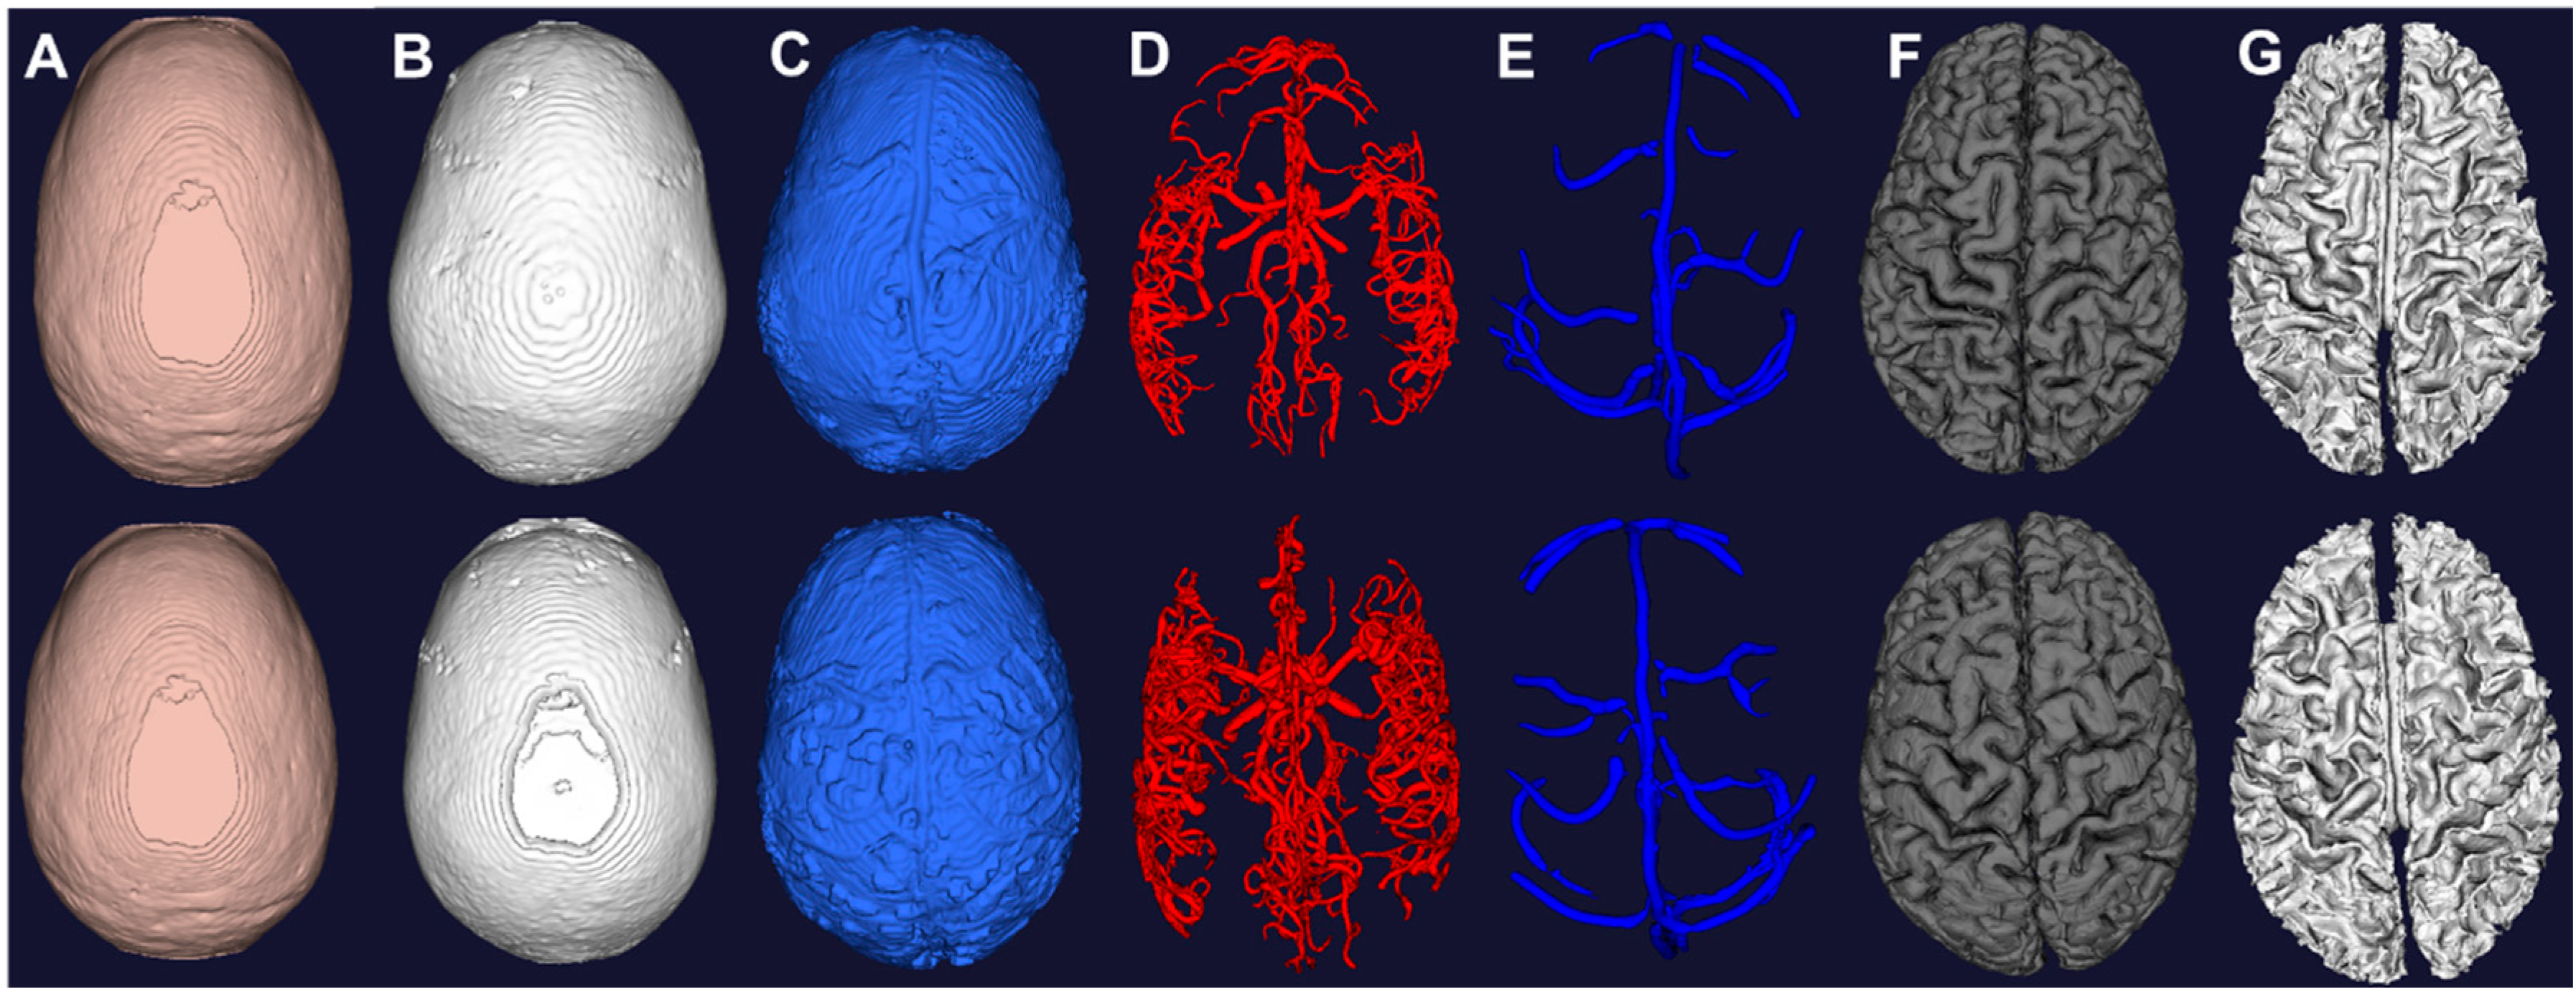

The T1 and T2 images in Figure 2 show clear delineation between the grey matter, white matter, and cerebrospinal fluid space. Figure 4 shows the segmented grey and white matter for the two subjects. The mesh vertices and faces are shown in Table 1. The meshes are generated with marching cubes along with binary images depicting the respective soft tissues. These images are used as input for skull and scalp segmentation.

Figure 4.

Computational meshes constructed from image segmentation of the two subjects. (A) Scalp from morphological operations of T1; (B) Skull from morphological operations of T1; (C) CSF from auto thresholding of T2; (D) Arteries from vessel filtering and segmentation of MRA; (E) Veins from vessel filtering and segmentation of MRV; (F) Grey matter from surface segmentation; (G) White matter from surface segmentation.

3.5. Whole Brain Mesh Generation

Figure 4 displays the individual meshes reconstructed from the proposed pipeline for the two subjects. Mesh metrics are evaluated in Table 1 and compared with physiological values [47,48,49,50,51,52]. The grey matter volume for both subject falls within the reported range of 710–980 mL. The white matter volume also for both subjects are also within reported values of 260–600 mL. The arterial and venous volume are slightly lower than reported values due to limited image resolution. The CSF volumes for both subjects in the lateral ventricles, third ventricles are fourth ventricles are all comparable to reported values. The scalp surface area for both subjects are approximately 10% higher than the reported value of 600 cm2. It demonstrates the ability of our pipeline to process image signals to reconstruct meshes for display and simulation. However, due to limited resolution and partial volume effect, the meshes intersect with each other at the boundaries which is not anatomically accurate. This inaccuracy appears mostly at the deep gyri, in which the small vessels are embedded with the cerebrospinal fluid. To compensate for the hardware limitations, we used the binary images to detect for intersections and excluded common voxels. One can also pursue Pons’s method to produce watertight meshes [25].